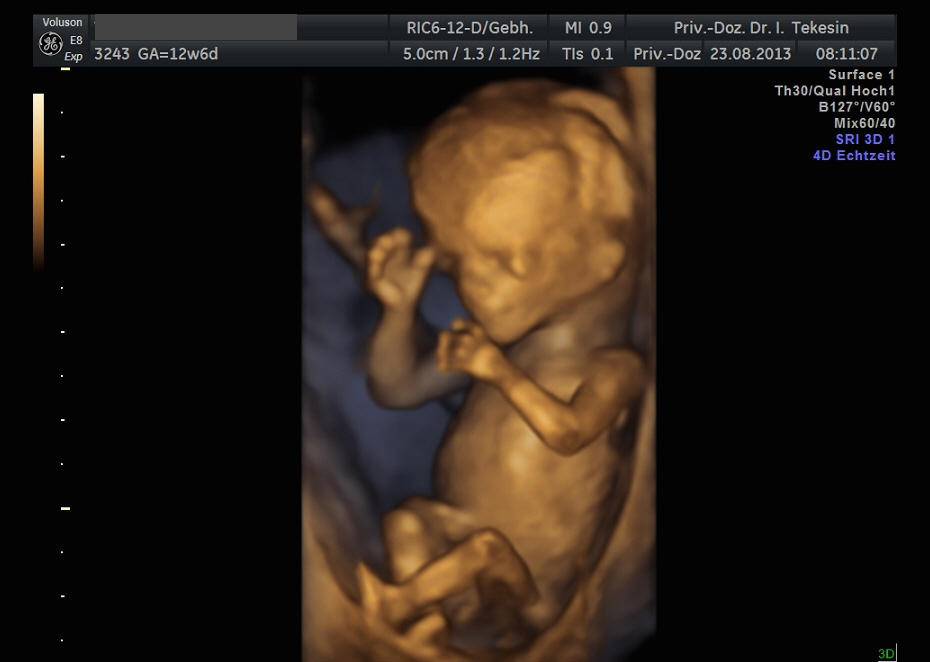

Kind in der 13. Woche (3D-Darstellung)